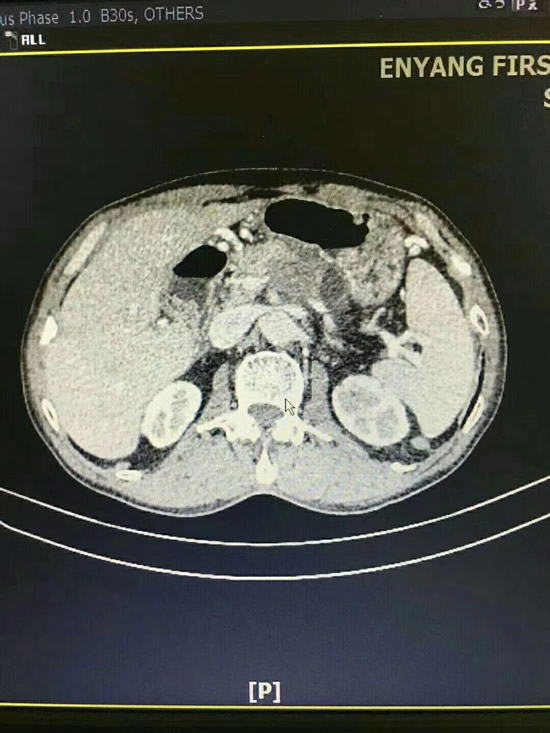

患者雷某因反复上腹疼痛,食欲减退,黄疸等不适入住我院。通过影像学检查,发现胆道下段占位并梗阻,考虑胆管下段癌可能性大,普外科牟坤主任带领团队认真研究了患者的病情,决定为其施行胰十二指肠切除术。当天,手术持续5个小时后,在医疗团队的共同努力下顺利完成该手术,成功切除胃1/3、胆总管、全部十二指肠、部分空肠、胰腺头部,手术取得了圆满成功,术后恢复满意。病理结果显示为胆管中分化腺癌,肿瘤切除完整,清扫彻底。